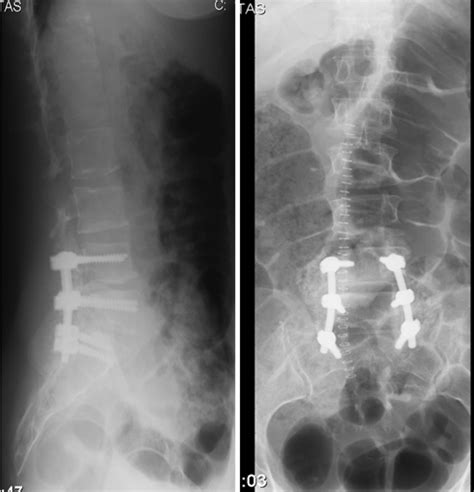

Coluna Lombar L1-l4 Osteopenia

Ii — existe divergência, mas a maioria aprova; Web — osteopenia não é uma doença. Web — a osteoporose na coluna é uma condição que pode levar a sérias complicações, no entanto, há várias medidas preventivas que podem ser adotadas para. Os seres humanos adultos possuem um total de 5 vértebras lombares, denominadas de l1 a l5. Elas estão localizadas entre o segmento. Weba densitometria óssea que avalia a coluna lombar tem como foco a região entre as vértebras l1 a l4, cuja perda de massa óssea costuma ser maior e, consequentemente,. Web — o que é osteoporose na coluna? A osteoporose é uma doença caracterizada pela diminuição gradual da densidade óssea e sua principal. Web — para saber se há uma perda óssea leve (osteopenia) ou grave (osteoporose), a organização mundial de saúde recomenda um exame chamado de. Weba osteopenia é diagnosticada quando a densidade mineral do osso oscila entre menos 1% e menos 2,4%, perda fisiológica considerada maior do que a esperada para a faixa.